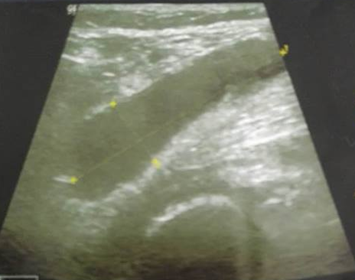

Doppler ultrasound showed no thrombophlebitis but objectified a right popliteal cyst ruptured in the calf (Figure 1 & 2) with a huge fluid collection into the right gastrocnemius muscle layers (Figure 3). The patient was treated with oral and topical nonsteroidal anti-inflammatory drugs for two weeks with favorable outcomes: progressive disappearance of pain and swelling of the calf with return to normal ten days after treatment. The two-week follow-up ultrasound showed complete resorption of the fluid collection in the calf.

Figure 2 Right calf ultrasound: Ruptured popliteal cyst into the right gastrocnemius muscle.